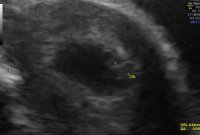

han tok nok flere målinger som i gjennomsnitt gav 6+3, mens denne ene målingen kanskje viste tilsvarende 6+6. I de fleste tilfeller er det uansett menstermin som "teller" frem til ordinær UL